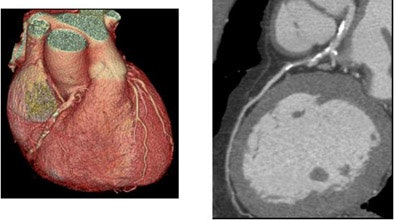

With a 0.35-second gantry rotation speed, the entire heart scan can be completed in less then seven seconds for a wide range of heart rates. Patient studies have confirmed the superior image quality obtained with the proposed method, he said. On each patient, four step-and-shoot half-scans were performed on a GE LightSpeed VCT64 scanner at 64 x 0.625 mm.

![]() |

| Patient scanned in four step-and-shoot half-scans on a GE LightSpeed VCT64 scanner at 64 x 0.625 mm. |